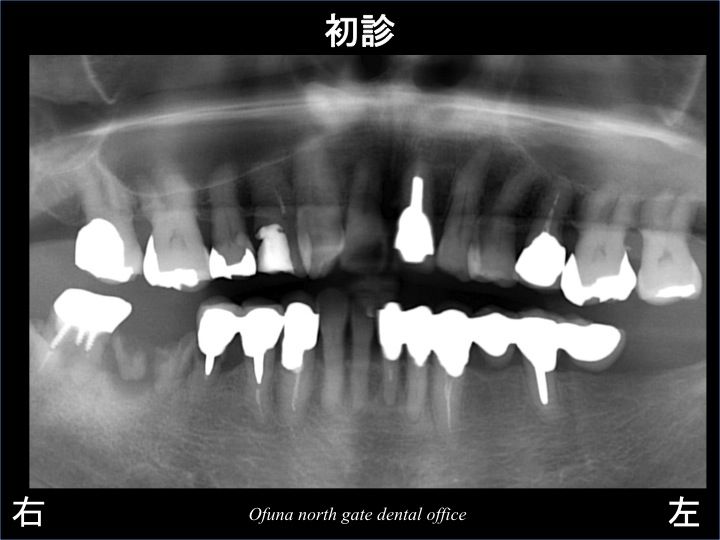

以下が初診時になります。

右下の奥歯の被せ物が取れたとのことで来院されました。

上記のレントゲン写真の丸で囲んだ部分を拡大したのが 以下になります。

欠損部(抜歯した歯の)手前の歯は、虫歯が非常に深く、

保存が厳しい状態です。

本来であれば、この虫歯の深い歯は、グラグラしても(取れても)おかしくない状態です。

しかし、この被せ物はグラグラして(取れていない)いません。

その理由として、手前の2歯と連結してあるのです。

つまり、3歯分連結した被せ物を装着してあるため、

虫歯が大きく進行していても 被せ物が取れたりすることがありませんでした。

また、この歯は神経がない歯です。

そのため、痛みもなく、患者様は問題をまったく感じていませんでした。

しかし、実際には 欠損部手前の歯は 保存が厳しい状態でした。

また、さらにその手前の歯も状態が悪い歯でした。